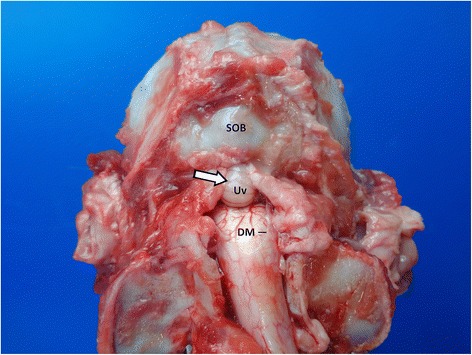

Fig. 1.

Caudodorsal view of the ventroflexed craniospinal junction in a dog after removal of paraxial muscles and laminectomie. Note the coning of the cerebellum in the foramen magnum. DM: Dura mater; SOB: supraoccipital bone; Uv: Uvula